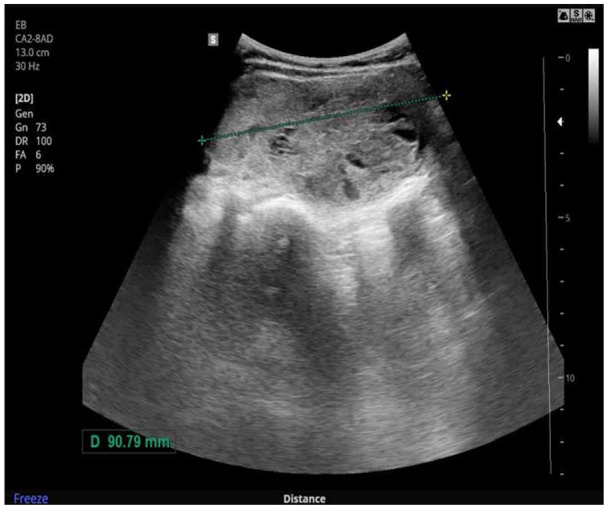

Sacral bone metastasis from primary follicular thyroid carcinoma (FTC) is rare. Most reported cases include factors indicative of thyroid origin, such as a history of treated thyroid cancer or newly identified thyroid nodules with malignant cytology. We herein report a 57-year-old woman with a metastatic sacral lesion of thyroid origin, initially misdiagnosed due to a false-negative fine-needle aspiration (FNA) cytology result of a thyroid nodule. The diagnosis was suspected based on an abnormally elevated serum thyroglobulin (sTg) level and confirmed through repeat core biopsy with thyroid-specific immunohistochemistry. This case highlights the limitations of FNA cytology in large thyroid nodules and underscores the potential role of sTg in diagnosing metastatic FTC in certain clinical scenarios. Thyroid carcinoma should be considered in the differential diagnosis of sacral metastases when the primary tumor is unknown.